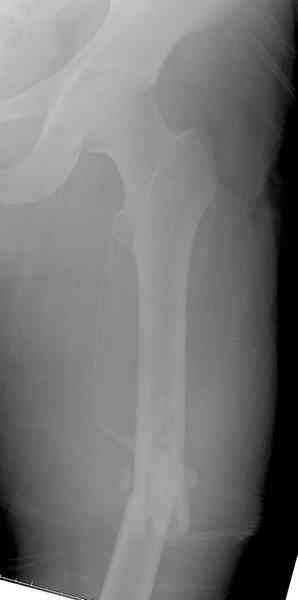

При высокоскоростных переломах редко можно встретить изолированную травму пилона, и в моей практике изолированные травмы большая редкость, поэтому, как дополнение к обсуждаемой теме, решил представить свежий, двухдневной давности случай.

Предыдущей сменой до 4:00 утра по поводу открытого перелома бедра, тибиал плато, пилон и надколенника сделана операция.

Пострадавшему 21 г., травма скоростная, после I&D с расширением раны, на бедре сделана операция ретроградным интрамедуллярным штифтом, остеосинтез с частичной резекцией надколенника и ушивание собственной связки.

На голень наружный фиксатор, рану на бедре ушили (рана была изнутри кнаружи всего 2 см). По протоколу травматических больных, до операции обследован ангиографически, (у больного дистально не смогли определить пульсацию) сосудистый хирург подтвердил проходимость на всем протяжении магистрального сосуда нижней конечности по снимкам ангиограмм.